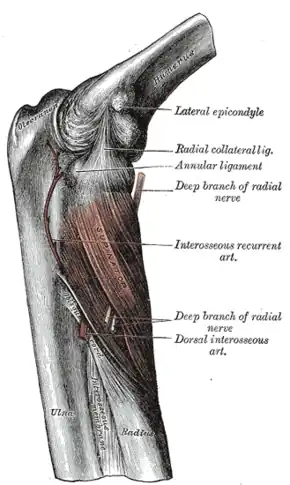

- The lateral epicondyle is a small, tuberculated eminence, curved a little forward, and giving attachment to the radial collateral ligament of the elbow-joint, and to a tendon common to the origin of the supinator and some of the extensor muscles.

The supinator.

The supinator.